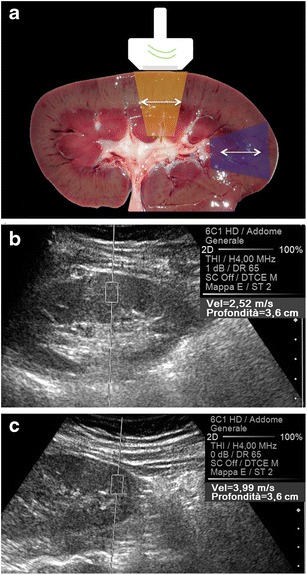

Fig. 9.

Effect of anisotropy on the speed of propagation of the shear waves. When the axis of the main US beam is parallel to the orientation of the vasa recta and Henle loops (orange box in a), the shear waves travel perpendicular to these structures and then move slowly (2.52 m/s in b). In the opposite condition (blue box in a), the SWV is higher (3.99 m/s in c)